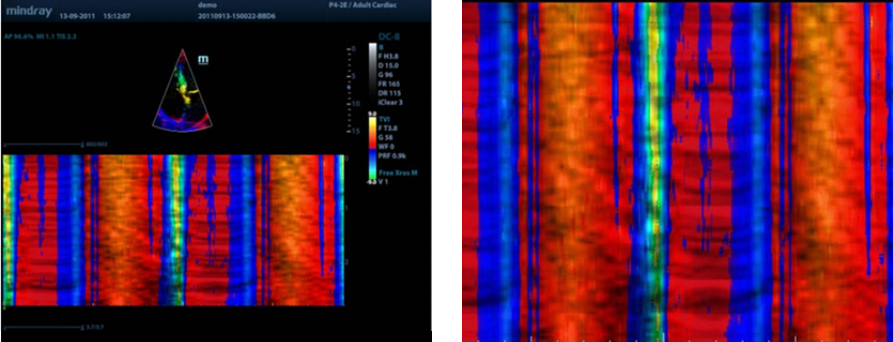

Free Xros CM?

Farkl? fazlarda miyokardiyal hareketin kesin olarak de?erlendirilmesi ve ayn? anda miyokardiyal senkronizasyonun belirlenmesi. YĂŒksek ?er?eve oran? ile kesin sonu?lar?n al?nmas?.

TDI

Doku Doppler G?rĂŒntĂŒleme, daha h?zl? ve do?rudan te?hisler i?in tĂŒm TDI modlar?n? sa?layarak, yerel miyokardiyal hareketi ve ?al??may? nicel olarak de?erlendirmeye izin verir.